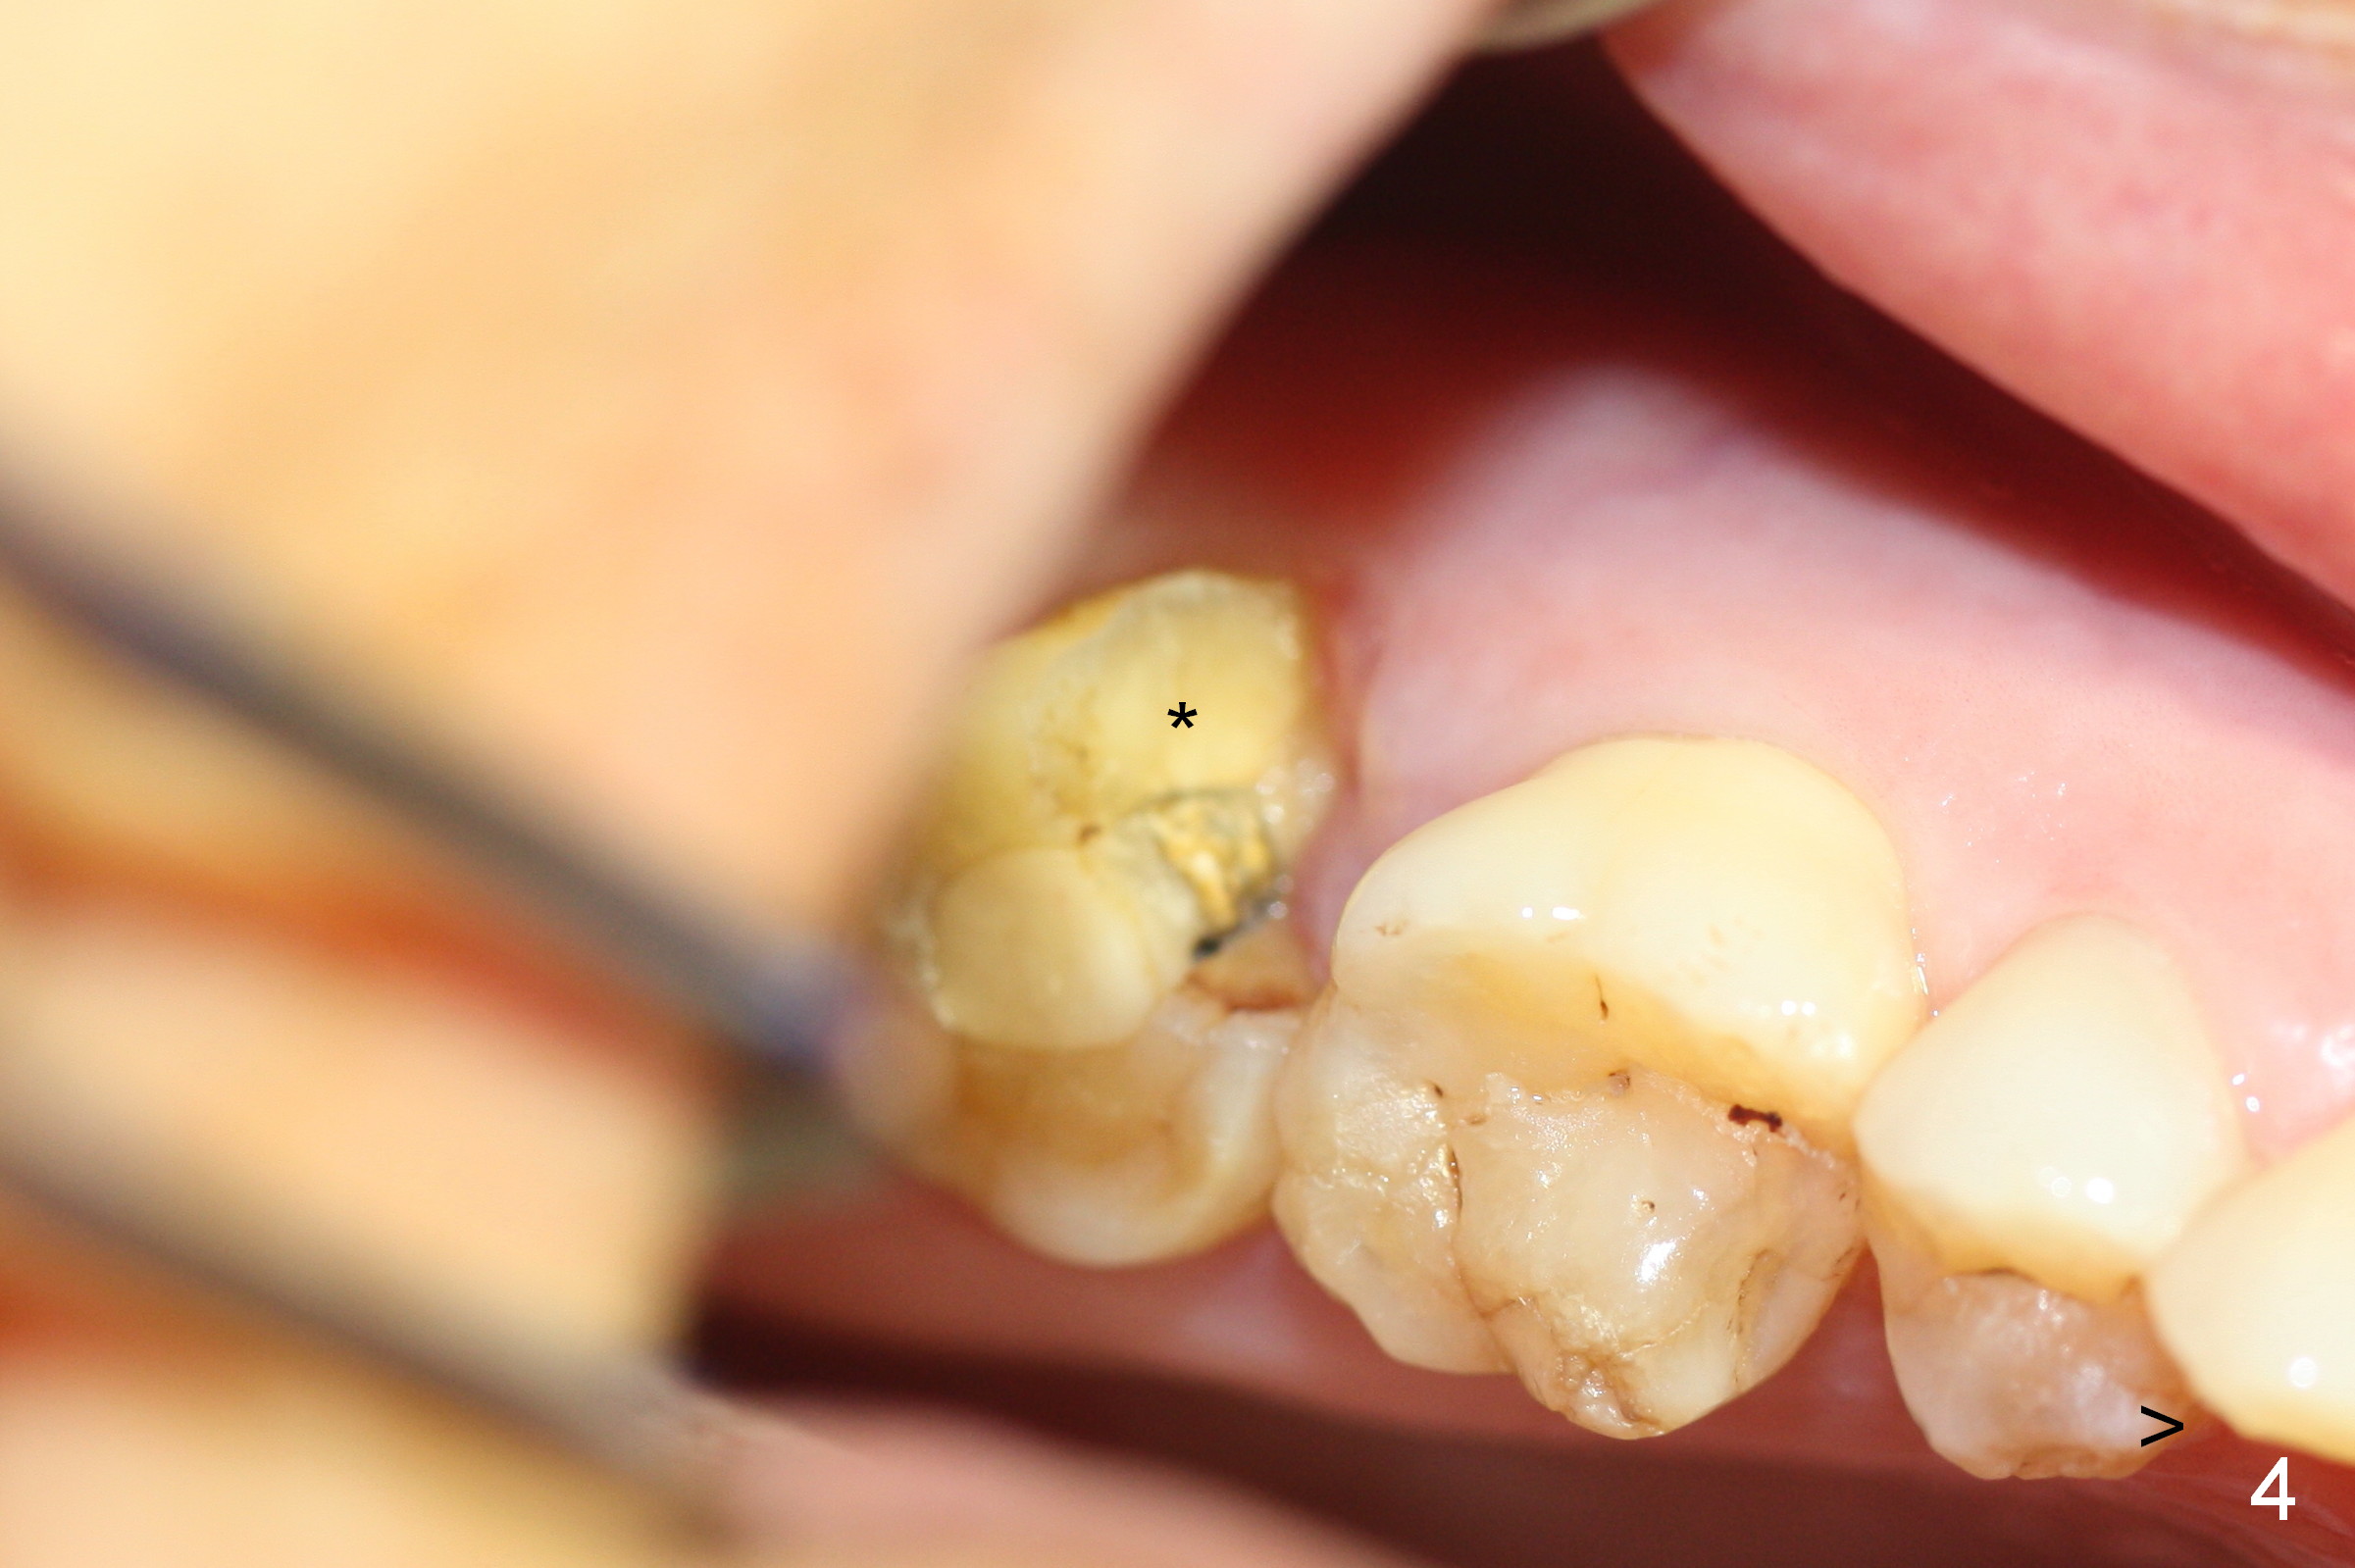

A 65-year-old lady is at early stage of Parkinson's disease and appears to be a bruxer. There are multiple chipped teeth, including #2 (Fig.1,4 *). She chooses implant over RCT retreat. A tissue-level implant (Fig.2) matches the root shape of the affected tooth better than a bone-level one (Fig.3), because of taper. The buccopalatal and mesiodistal dimensions of the extraction socket are 11 and 8 mm, respectively (Fig.5,7).